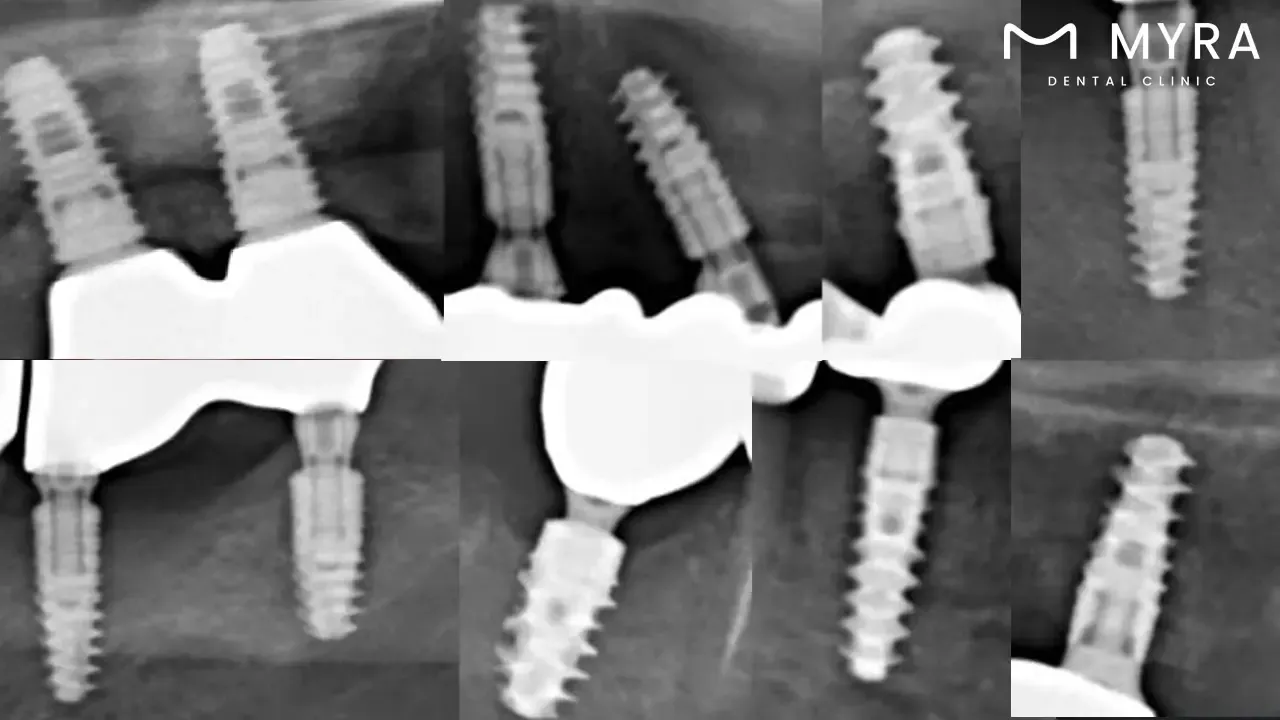

Endosteal Implants: Endosteal implants involve the surgical placement of artificial tooth roots directly into the jawbone, resembling the roots of a genuine tooth. It is a type of implant known for its stability and functionality, with a success rate reaching approximately 95%.

Implant-Supported Bridgework: Implant-supported bridgework utilises implants as stable anchors for a bridge with artificial teeth, commonly made of titanium. It is a method that provides durability, with a success rate leading to longevity exceeding ten years.

All on 4 Dental Implants: The All on 4 dental implant procedure supports a full arch of prosthetic teeth, minimising the need for extensive bone grafting. All on 4 implants in Turkey have a predicted lifespan of 20–25 years, or even a lifetime, with a success rate of 99%.

Yes, different types of dental implants impact the overall limit. A patient's bone composition and general oral health are two factors deciding between endosteal, subperiosteal, and zygomatic implants. Their effects on the total limit differ, and each type tackles a different set of problems. The objective is to personalise the implant therapy according to the patient's specific requirements, taking into account the pros and cons of each implant type to maximise stability, functionality, and aesthetics.

Most of these are endosteal, surgically implanted into the jawbone. The quality and density of the accessible bone affect the maximum number of dental implants. Endosteal implants are more stable, meaning a higher max number is possible when the bone is strong.